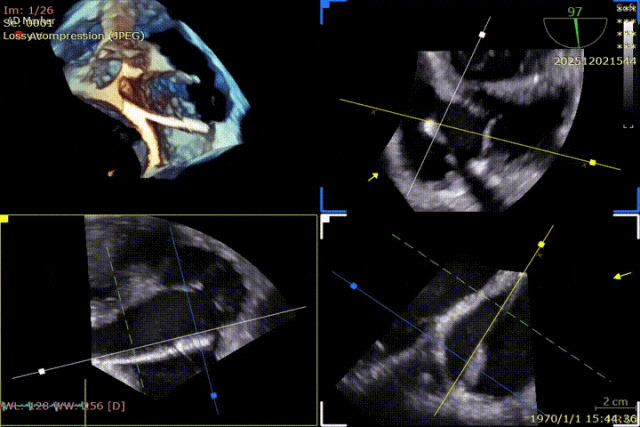

During the procedure, close collaboration was maintained with Dr. Yang Yan (anesthesiologist, Department of Anesthesiology) and Dr. Niu Ming (echocardiography specialist, team of Director Zhai Hong, Department of Cardiac Ultrasound). Guided by transesophageal echocardiography and assisted by DSA imaging, the tricuspid annular structure and regurgitation jet direction were precisely assessed. Ultimately, two 12T K-Clip® devices were successfully implanted. Immediate postoperative echocardiographic evaluation showed a significant reduction in tricuspid regurgitation from 4+ preoperatively to 1+, with a marked decrease in annular area. The surgical outcome was satisfactory.

Echocardiographic: Severe tricuspid regurgitation (grade 4+), with the regurgitant jet mainly located at the posteroseptal and central regions. No significant dilatation of the tricuspid annulus is observed. Mild myxomatous degeneration of the tricuspid leaflets is present, showing Barlow-like morphology, with leaflet prolapse of 3.7 mm in height.

Preoperative Regurgitation: 4+

Annulus Area: 11.3 cm²

Postoperative Regurgitation: 1+

Annulus Area: 4.9 cm²